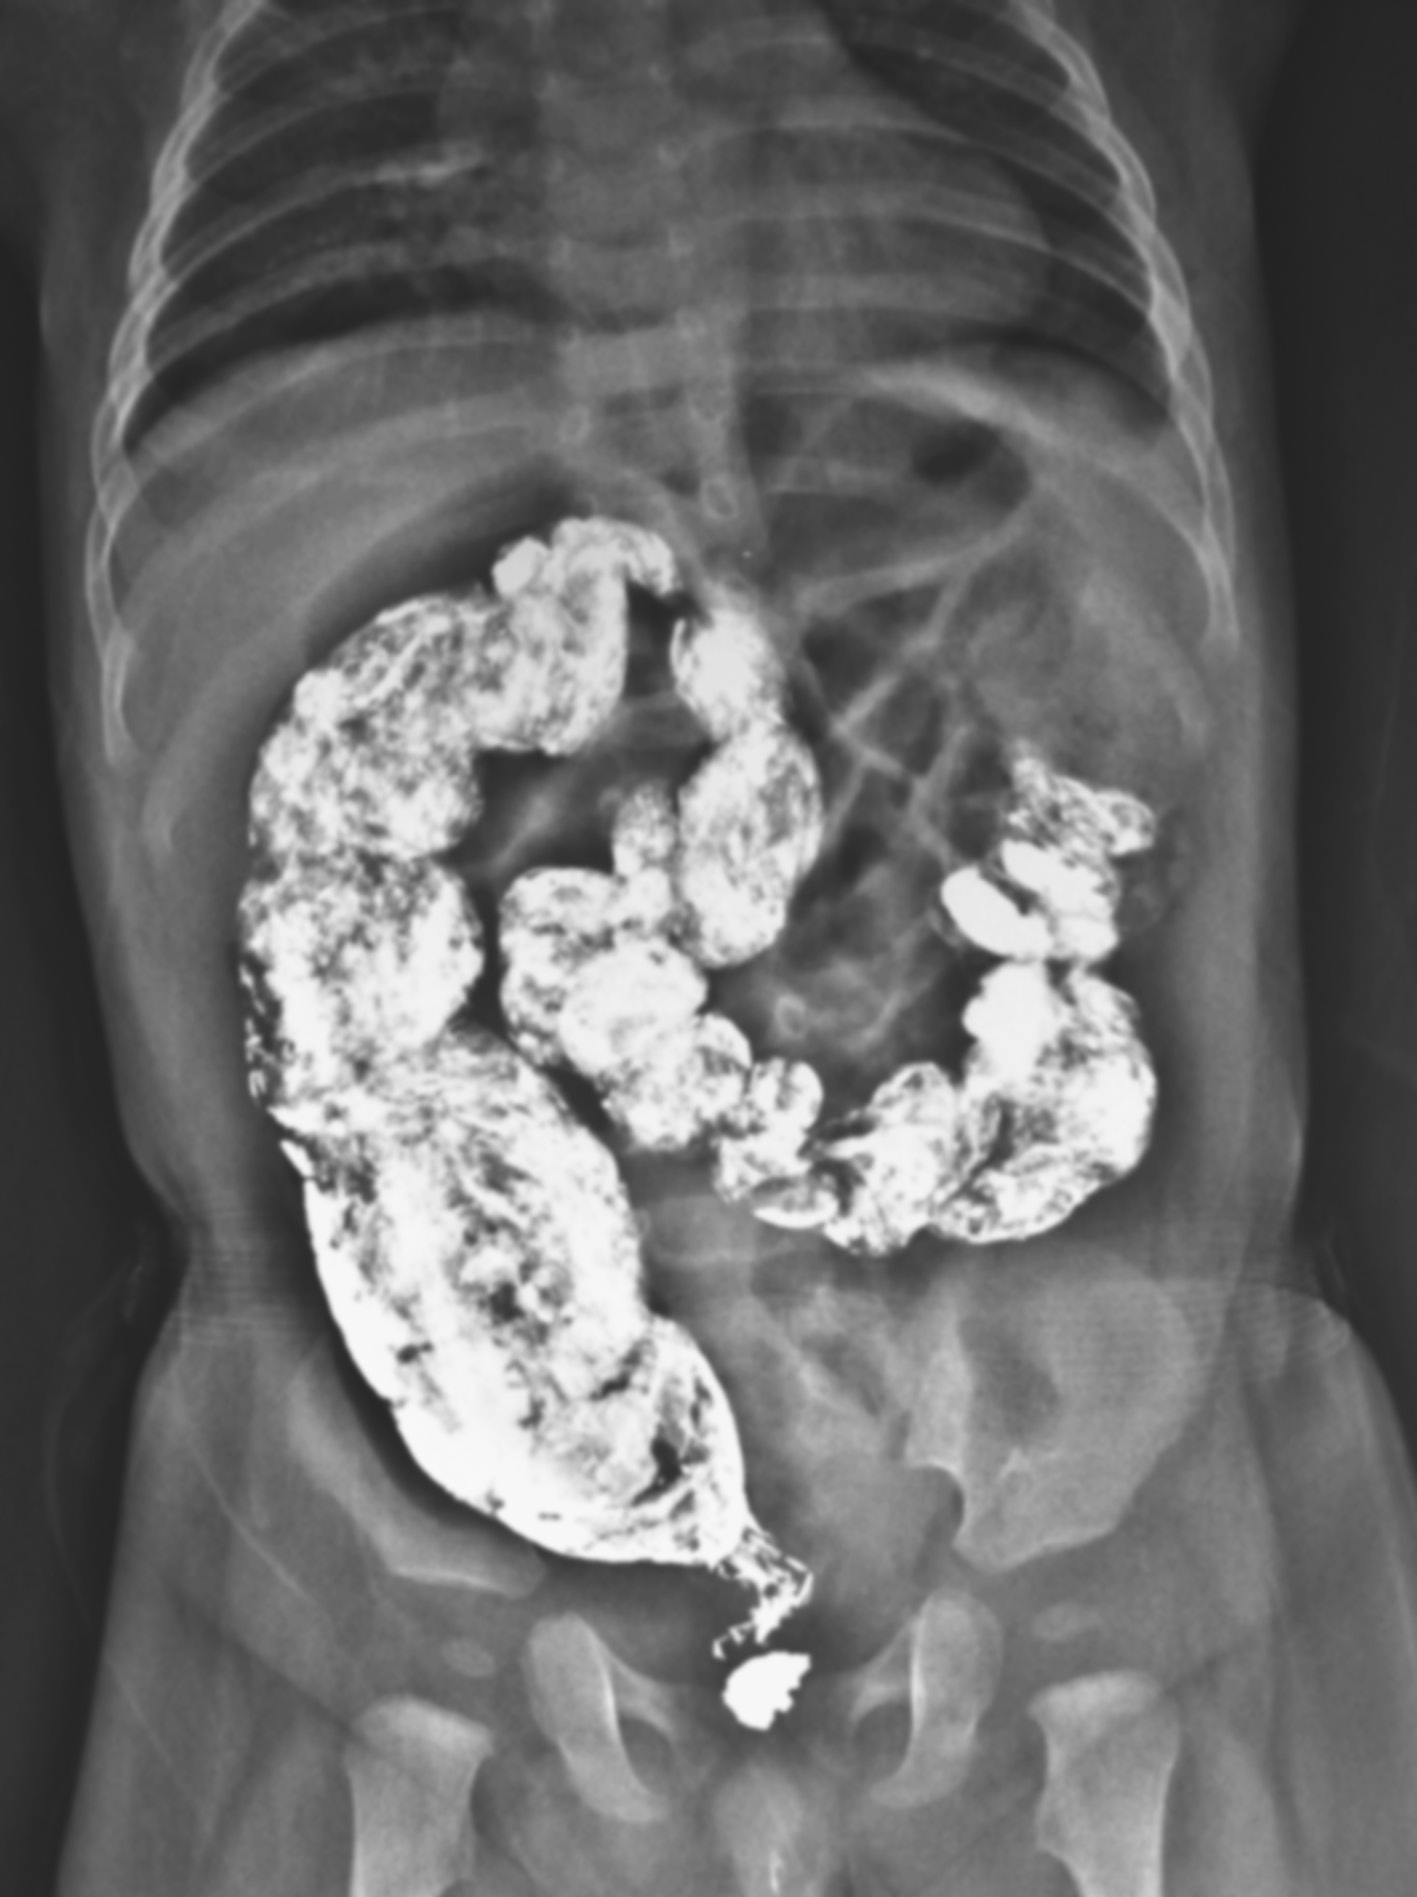

图3-2 新生儿先天性巨结肠症腹部平片

肠管广泛积气,结肠扩张不典型。